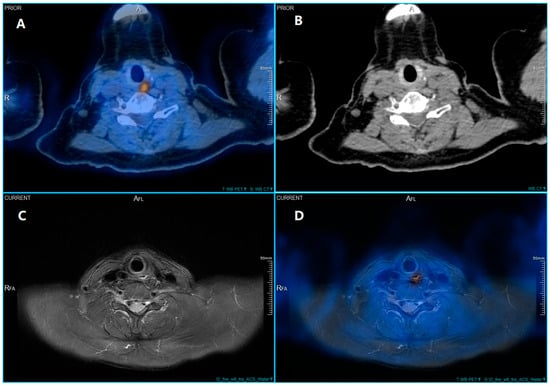

In addition to standardized lateral cephalometric radiographs, comprehensive assessment using dental cone-beam computed tomography (CBCT) and CT has become commonplace in the diagnosis and treatment of jaw deformities. Simulation based on cephalometr...